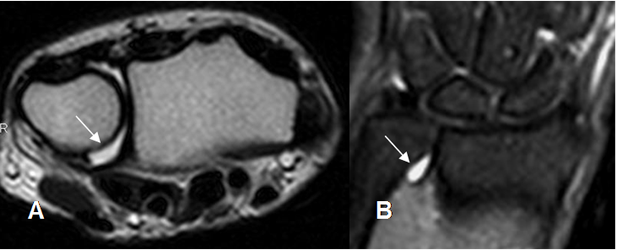

La presencia de líquido rodeando la articulación radioulnar distal, es un importante signo secundario de ruptura. (6). (Fig 78).

Fig 78. Ruptura del FCT.

A: RM axial en T2 y B: RM coronal en STIR. Presencia de líquido en la articulación radioulnar distal, por ruptura no mostrada del FCT.